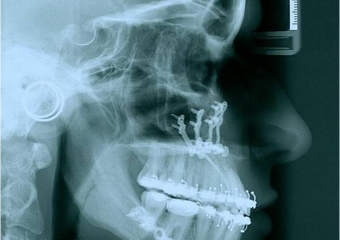

Telerradiografia inicial - Clínica Cliniface

Telerradiografia inicial